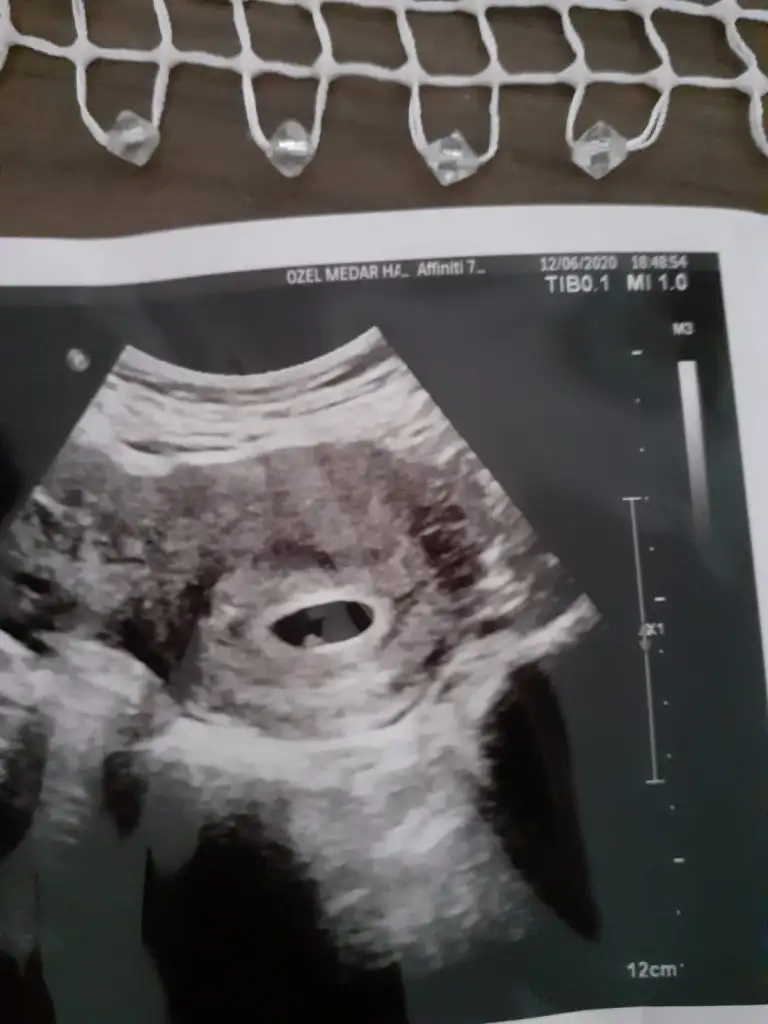

Inşallah canim hayırlısı bugün yine kontrolüm vardı maşallah kocaman olmuşHaftaniza göre bebek gelismis baya erkek çocukları daha çabuk gelişir derler

Allah gönlünüze göre versin insallah kızınız var galibaInşallah canim hayırlısı bugün yine kontrolüm vardı maşallah kocaman olmuş